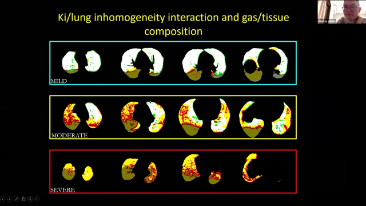

Combinant oxygĂŠnothĂŠrapie Ă haut dĂŠbit (OHD), ventilation non invasive (VNI) et ventilation invasive (VI) les ventilateurs de la sĂŠrie SV 3 en 1 offrent des performances stables, des fonctions polyvalentes et une simplicitĂŠ d'utilisation. Des caractĂŠristiques exceptionnelles de ventilation protectriceet de nombreux outils d'aide Ă la dĂŠcision sont con?us pour rĂŠduire le risque d'infection croisĂŠe et faciliter le travail quotidien du personnel soignant.